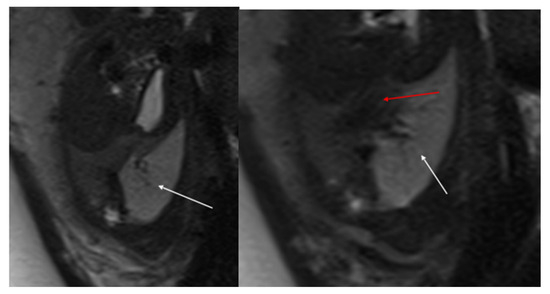

In type 1, the right main bronchus (RMB) terminates in the right upper lobe (ULB), while the intermediate bronchus abnormally arises from the left main bronchus (LMB), creating a pseudocarina; either the right bronchus or a bridging bronchus generally supplies the middle lobe [14]. Type 2 is often associated with right lung hypoplasia (Figure 9). In this type, the RMB may be absent or end in a diverticulum. The entire right lung is ventilated by a displaced RMB originating from the LMB, forming a pseudocarina [14].

In this condition, the carina faces thoracic vertebrae T4 and T5; the pseudocarina, instead, is at the T6–T7 level and has an inverted T appearance [14].

Figure 9. Bridging bronchus type 2. Non-contrast CT coronal (a) and VR (b) images reveal the RMB ending in a diverticulum. The right lung is ventilated by a displaced RMB arising from the LMB, forming a pseudo-carina, that is at the T6–T7 level and has an inverted T appearance.